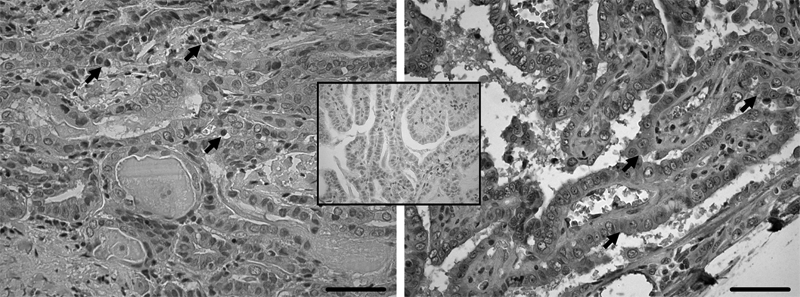

La intensidad de expresión proteica de los distintos marcadores en los cortes histológicos estudiados fue variable, detectándose algunas diferencias importantes en la expresión de ellos en el núcleo y en el citoplasma de las células tumorales (Figura 3).

En el caso de la tinción nuclear, no hubo diferencias en la expresión de NIS, cMet y TIMP; sin embargo, EphrinB2 se expresó con significativa menor intensidad (p < 0,05) en el grupo de tumores sin metástasis ganglionares (Figura 4).

Al analizar los resultados de expresión en citoplasma, se observó una leve menor expresión de NIS y TIMP, sin alcanzar significación estadística (p = 0,13 y 0,15, respectivamente) en el grupo de tumores con metástasis, pero se objetivó una mayor expresión (p < 0,05) de ephrinB2 en este grupo (Figura 5).

Figura 3. Corte histológico con aumento 40x de pieza operatoria de cáncer papilar de tiroides, con tinción inmunohistoquímica para EphrinB2 de predominio nuclear (flechas en foto izquierda) y citoplasmático (flechas en foto derecha). El recuadro central muestra el control negativo. Barras = 50 mm.